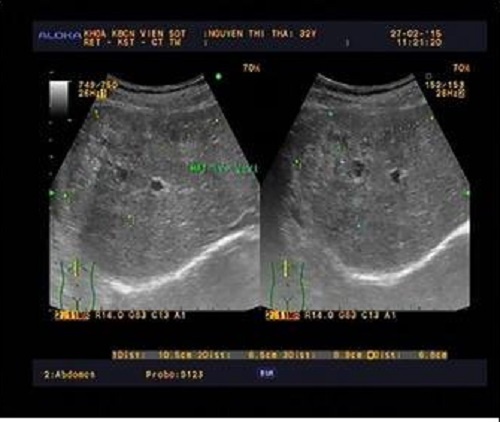

| Các bác sĩ có thể nhìn thấy hình ảnh sán lá gan làm tổ rất rõ qua phim chiếu chụp. Ảnh: BSCC. |

Tại Viện Sốt rét Ký sinh trùng Côn trùng Trung ương, sau khi xem phim chiếu chụp các bác sĩ không khỏi kinh ngạc khi thấy một ổ sán đang làm tổ trong não bệnh nhân. Đáng sợ hơn, sán làm tổ gây ổ áp xe, phát triển chèn vào não thất. Bác sĩ quyết định phải tiến hành phẫu thuật ngay cho bệnh nhân, tránh nguy hiểm đến tính mạng. Sau một tuần điều trị, sức khỏe bệnh nhân đã ổn định.